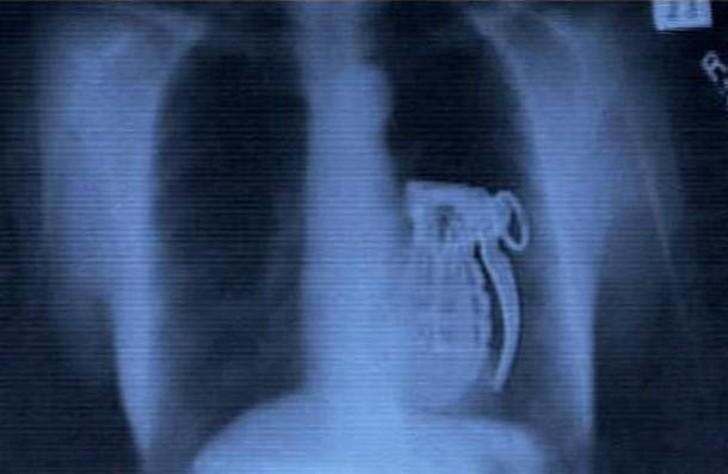

14. Граната.